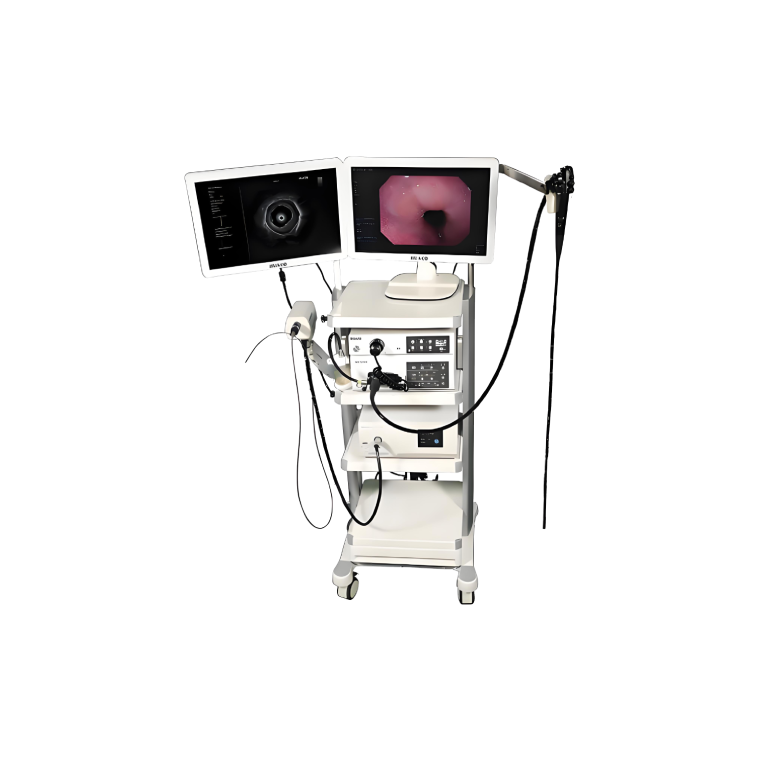

Lepu yüksek teknoloji tıbbi cihazlar ve ekipmanları

Kardiyovasküler tıbbi cihazlarda lider lepu medical, 190 iştiraki küresel bir ağa sahiptir. 214 ce sertifikalı ve 34 fda onaylı ürünle lepu, tıbbi cihazları, ilaçları, sağlık hizmetlerini ve kalp bakımı için mobil sağlık hizmetlerini kapsayan entegre bir platform kuruyor. Şirket sırasıyla 2009 ve 2022 yılında shenzhen borsası (300003) ve İsviçre borsasında listelenmiştir.